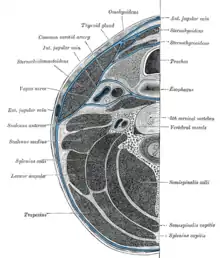

Rapports

La thyroïde présente les rapports anatomiques suivants :

- ventralement : muscles cervicaux superficiels ;

- latéralement : nerfs récurrents et axes vasculaires jugulo-carotidiens ;

- dorsalement : larynx au pôle supérieur et trachée cervicale au pôle inférieur.

Les quatre parathyroïdes ont des positions variables, mais se situent généralement aux quatre pôles thyroïdiens.